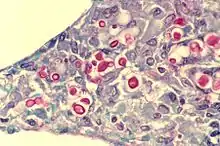

Cryptococcus neoformans (red after staining) in human lung

- A taxonomic species within the family Tremellaceae – a fungus species that causes cryptococcosis, often fatal in humans.